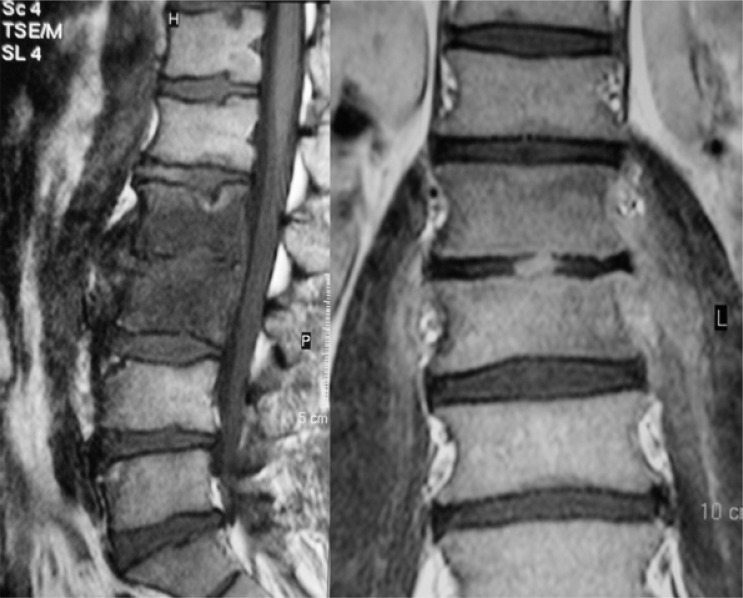

Brucellosis is a zoonotic disease caused by Gram-negative bacteria of the Brucella genus that can be acquired through contact with a contaminated animal or its secretions. The course of the disease can be acute, chronic, or persistent. Axial skeleton and central nervous system (CNS) are among the most common affected locations and may be involved in each of the forms. Due to the varying clinical picture of the disease, diagnosis is made mainly on the basis of laboratory examinations that detect specific IgM and IgG antibodies in blood or other biological material and/or cultures. Imaging methods, especially magnetic resonance imaging, can aid in establishing proper diagnosis, monitoring of the disease and, to some extent, enable differential diagnosis before obtaining the laboratory tests results. The aim of this review is to present imaging features of Brucella infection of the spine and CNS and provide the recent advancements in the field.

Abstract Image